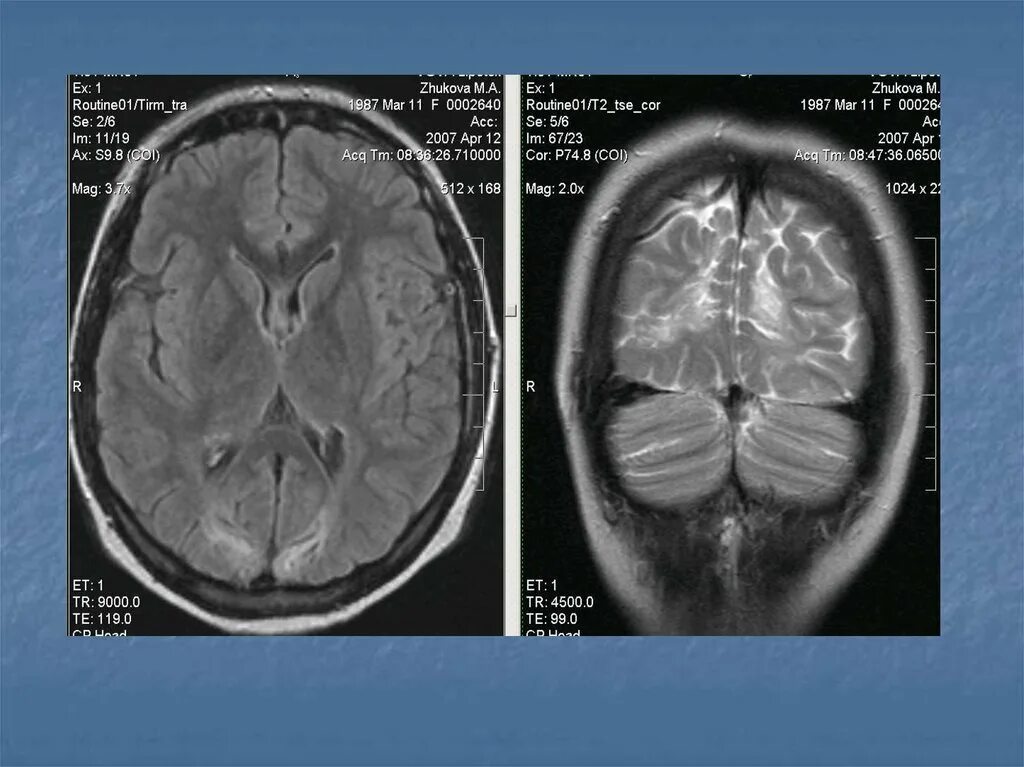

Диффузные изменения вещества головного мозга